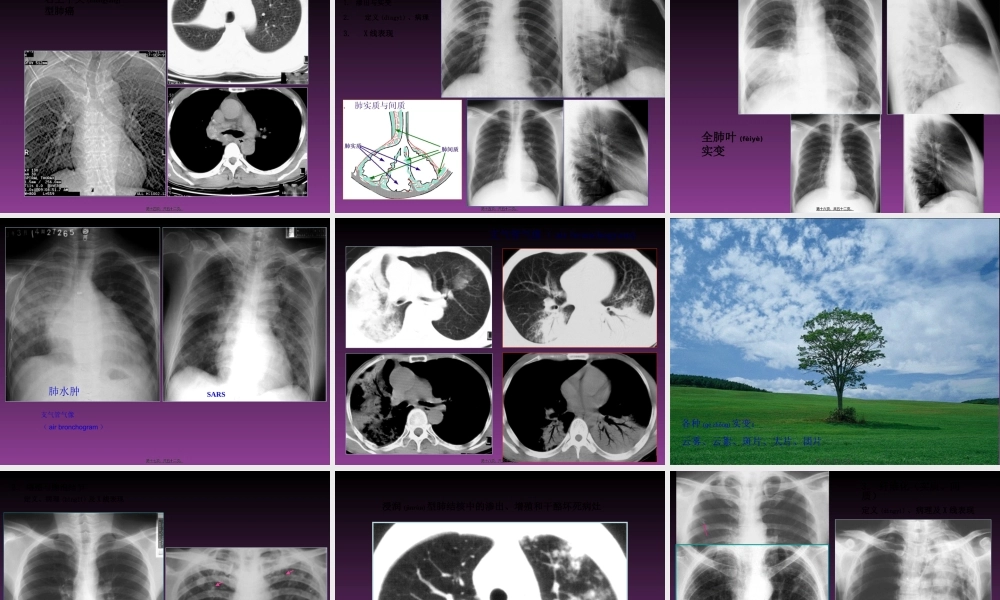

呼吸系统基本(jīběn)病变的X线表现X线征象(表现)--基本病变(bìngbiàn)--病变(bìngbiàn)性质--疾病诊断临床诊断:临床表现(病史、体检等)--一种、几种可能的诊断;影像资料等各种辅助检查--验证或否定(fǒudìng)、排除影像诊断:影像征象--病理基础--疾病可能;结合临床表现--最合理的解释第一页,共五十二页。第一页,共五十二页。(一)支气管改变病因,常规X线主要为肺的间接(jiànjiē)表现1.阻塞性肺气肿--活塞机制2.(1)局限性第二页,共五十二页。第二页,共五十二页。左侧(zuǒcè)一侧性阻塞性肺气肿左下肺局限性阻塞性肺气肿第三页,共五十二页。第三页,共五十二页。代偿(dàichán)ɡ性肺气肿第四页,共五十二页。第四页,共五十二页。(2)弥漫性第五页,共五十二页。第五页,共五十二页。第六页,共五十二页。第六页,共五十二页。肺气肿第七页,共五十二页。第七页,共五十二页。2.阻塞(zǔsè)性肺不张--完全阻塞(zǔsè),肺外压迫,肺内疤痕收缩;一侧性,肺叶,肺段,肺小叶;第八页,共五十二页。第八页,共五十二页。第九页,共五十二页。第九页,共五十二页。右上叶不张第十页,共五十二页。第十页,共五十二页。右下叶不张左下叶不张第十一页,共五十二页。第十一页,共五十二页。右中叶(zhōngyè)不张第十二页,共五十二页。第十二页,共五十二页。一侧性肺不张第十三页,共五十二页。第十三页,共五十二页。右上中央(zhōngyāng)型肺癌第十四页,共五十二页。第十四页,共五十二页。(二)肺部病变1.渗出与实变2.定义(dìngyì)、病理3.X线表现第十五页,共五十二页。第十五页,共五十二页。全肺叶(fèiyè)实变第十六页,共五十二页。第十六页,共五十二页。SARS肺水肿支气管气像(airbronchogram)第十七页,共五十二页。第十七页,共五十二页。支气管气像(airbronchogram)第十八页,共五十二页。第十八页,共五十二页。各种(ɡèzhǒnɡ)实变:云雾、云絮、斑片、大片、团片第十九页,共五十二页。第十九页,共五十二页。2.增殖与腺泡结节定义、病理(bìnglǐ)及X线表现第二十页,共五十二页。第二十页,共五十二页。浸润(jìnrùn)型肺结核中的渗出、增殖和干酪坏死病灶第二十一页,共五十二页。第二十一页,共五十二页。3.纤维化(实质、间质)定义(dìngyì)、病理及X线表现第二十二页,共五十二页。第二十二页,共五十二页。第二十三页,共五十二页。第二十三页,共五十二页。4...